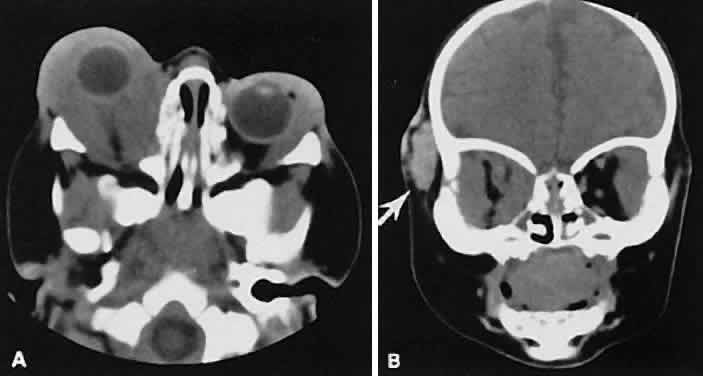

| The edema and inflammatory infiltrate that accompany infections are indistinguishable

from that associated with orbital inflammations. The presence

of sinus disease, however, is a more constant feature with infections, because

the sinus represents the infectious nidus in most cases (Fig. 9). In addition to the frequent appearance of sinus disease, the adjacent

EOM is invariably enlarged. Less often, orbital infections may be transmitted

through the blood, related to a retained foreign body, or spread

from the lids. Chandler and colleagues47 classified orbital infections into five groups. Group 1 (preseptal cellulitis) represents

inflammatory edema and reflects congestion of venous

outflow. Group 2 has actual orbital infiltration/edema with mass effects

and functional deficits. Group 3 includes patients with subperiosteal

abscesses. Most of these dome-shaped subperiosteal abscesses are

located along the medial wall. Group 4 includes patients with orbital

abscesses who may display a ring-enhancing lesion with mass effect. Group 5 represents

intracranial extension of the inflammation into the

cavernous sinus or sinuses, which appear engorged and opacified. Harris48 related the clinical course of patients with subperiosteal abscesses to their CT scans. The sub-periosteal material could not be predicted from the size or the relative radiodensity of the collections on the scan. Serial scans also showed enlargement of the abscess during the first few days of intravenous antibiotic therapy, regardless of the ultimate response to therapy. |